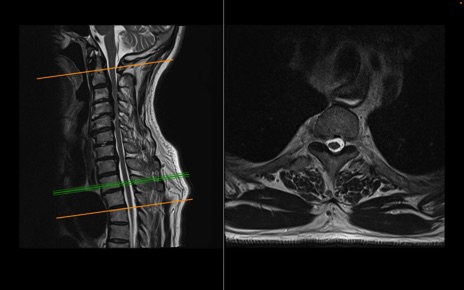

頚椎MRI

T2WI(横断像)

T2WI(矢状断像)